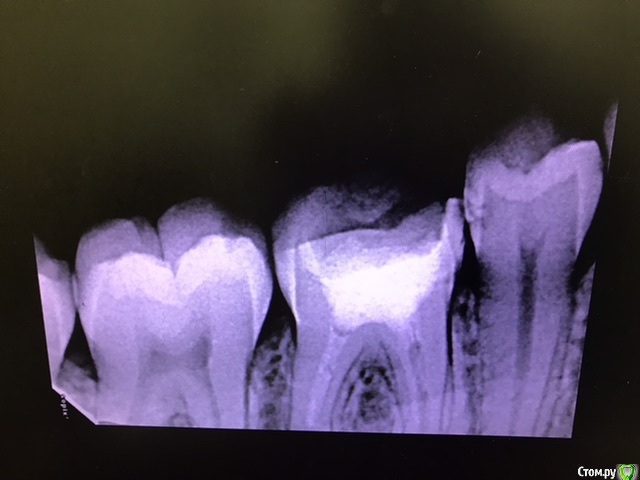

В середине марта обратилась на перелечивание каналов с гранулемой в 46 зубе.

Прикрепляю рентген до, 3 рентгена после первого лечения, рентген после установки гуттаперчевых штифтов. Также есть КТ до перелечивания, вдруг кто-то заинтересуется.

Добрый день. По снимкам  после все в пределах нормы.